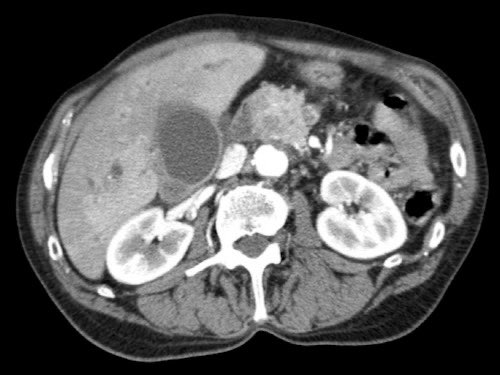

CT axial cho thấy:

- Khối u ở thân tụy (đầu mũi tên trắng).

- Tiếp xúc khu trú < 90º với động mạch mạc treo tràng trên (SMA).

- Tiếp xúc rộng hơn từ 90º – 180º với SMV, SMV bị hẹp nhẹ và biến dạng (mũi tên vàng).

- Giãn ống tụy